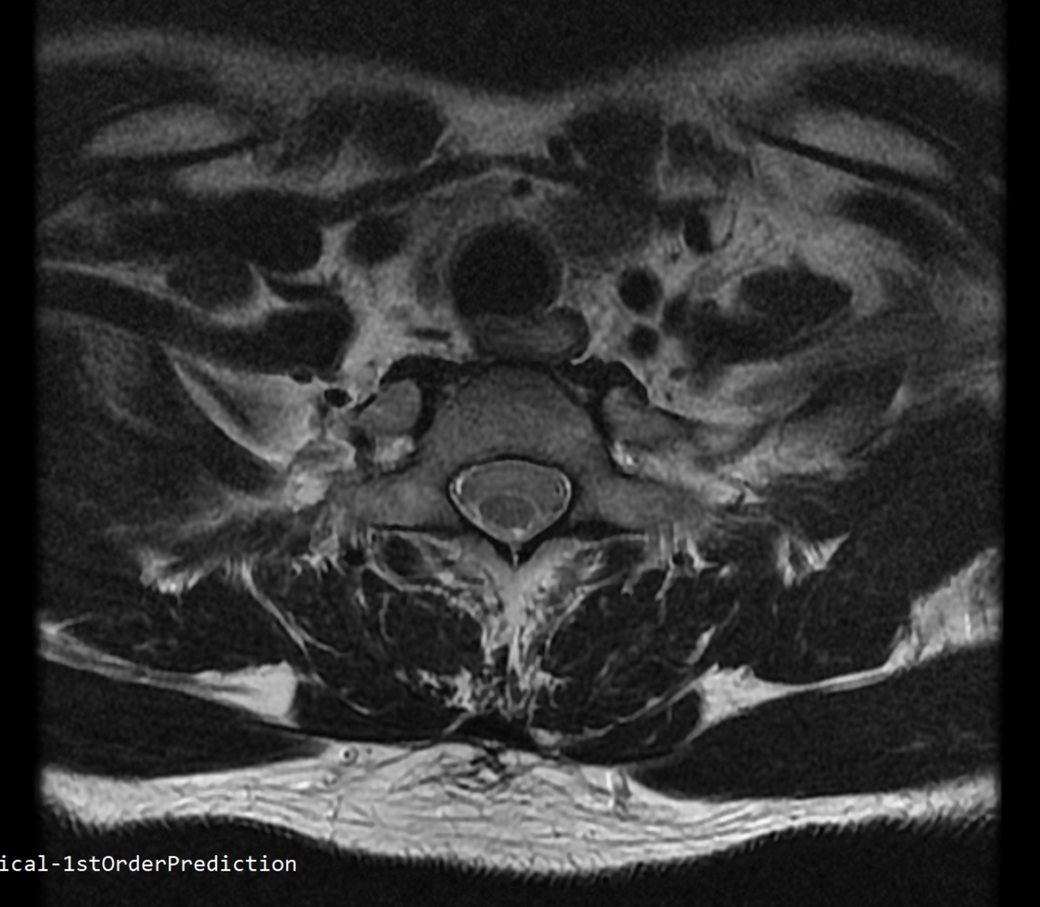

안녕하세요 목 경추 상단부터 순서대로 mri 촬영인데요

전체적으로 봐주시면 감사하겠습니다

하단8번 신경쪽도 나오는건지.. 봐주시면 감사하겠습니다

• 4번 째 사진